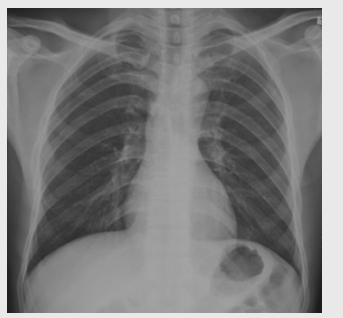

01卷-3.根據下圖請做出正確診斷

A.正常心臟

B.心肌病(普大心)

C.風濕性心臟病(梨型心)

D.主動脈型心(靴型心)

正確答案:B/D/C/A/A/D/D/D